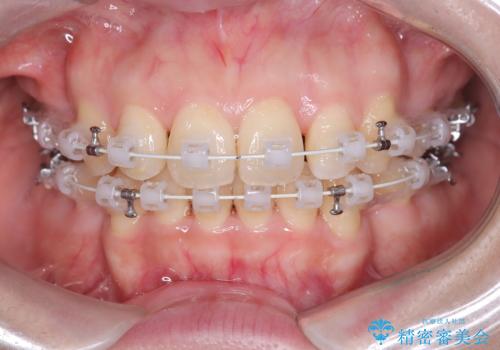

- 矯正装置

- ワイヤー(審美装置)

上下左右の4番(第一小臼歯)を抜歯をし審美ワイヤー装置で治療を行いました。

抜歯矯正により歯列のデコボコ(叢生)が改善し、前歯の突出も解消されたことで口元が下がり、すっきりとした印象となりました。